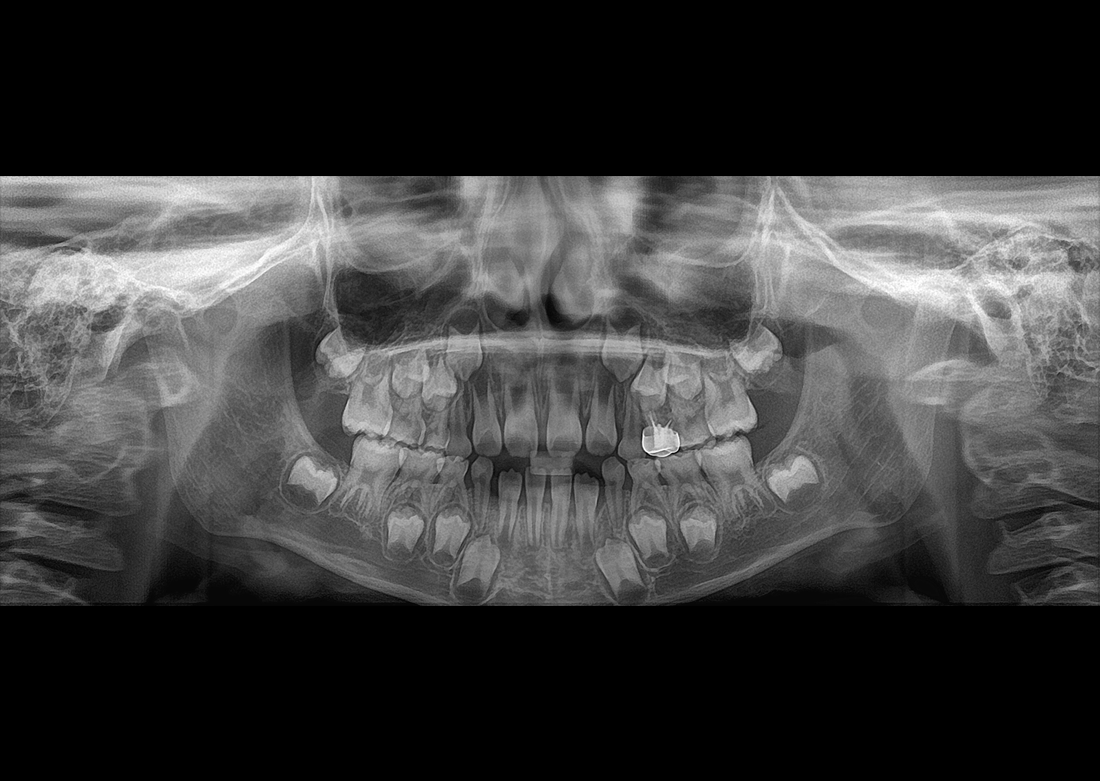

The Papaya 3D Premium/Ultra is the newest generation in a long line of Genoray products designed to produce accurate diagnostic images with wider treatment applications including implants, endo, ortho, airway, TMJ, and orthognathic surgeries. Optimized acquisition PC/Monitor/Accessories, model scan/STL converter, and perpetually licensed software suites included.

- Papaya 3D Premium CBCT: Min 4x5 to Max 16x14 FOV

- Papaya 3D Ultra CBCT: Min 4x5 to Max 23x24* FOV